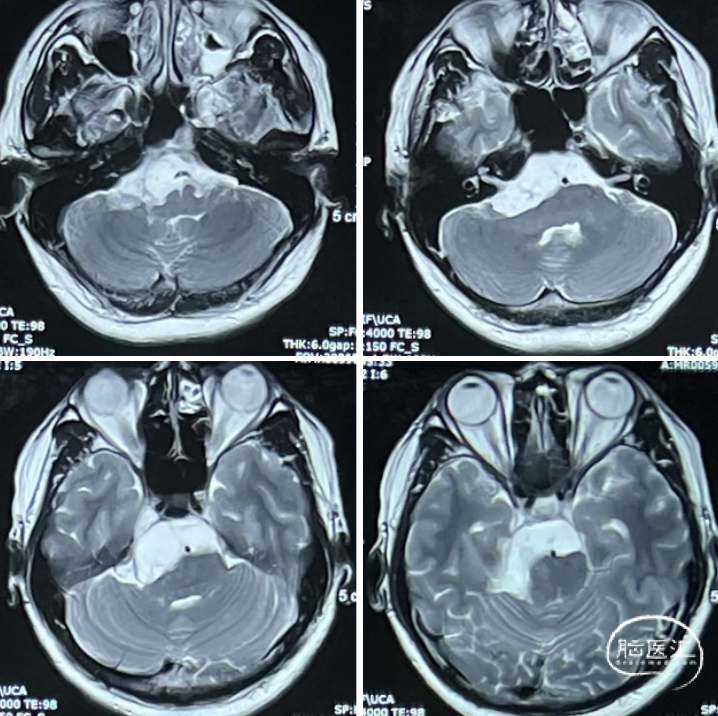

患者情况

查体:右侧听力下降。